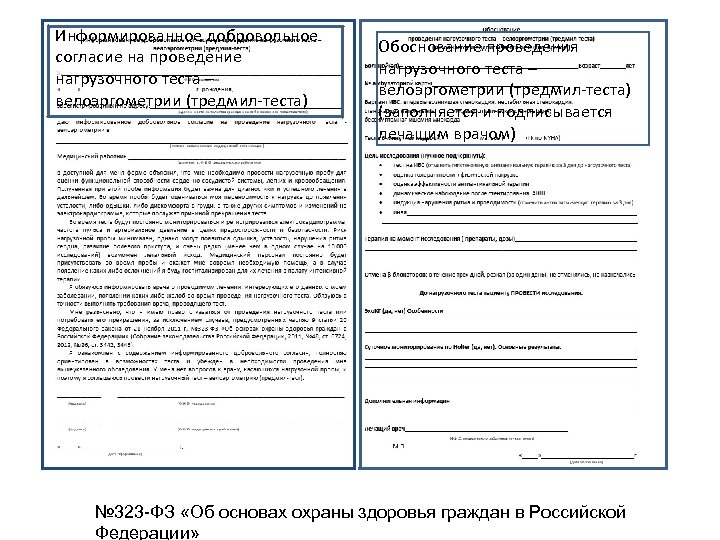

Информированное добровольное согласие на проведение нагрузочного теста – велоэргометрии (тредмил-теста) Обоснование проведения нагрузочного теста – велоэргометрии (тредмил-теста) (заполняется и подписывается лечащим врачом) № 323 -ФЗ «Об основах охраны здоровья граждан в Российской Федерации»

Информированное добровольное согласие на проведение нагрузочного теста – велоэргометрии (тредмил-теста) Обоснование проведения нагрузочного теста – велоэргометрии (тредмил-теста) (заполняется и подписывается лечащим врачом) № 323 -ФЗ «Об основах охраны здоровья граждан в Российской Федерации»